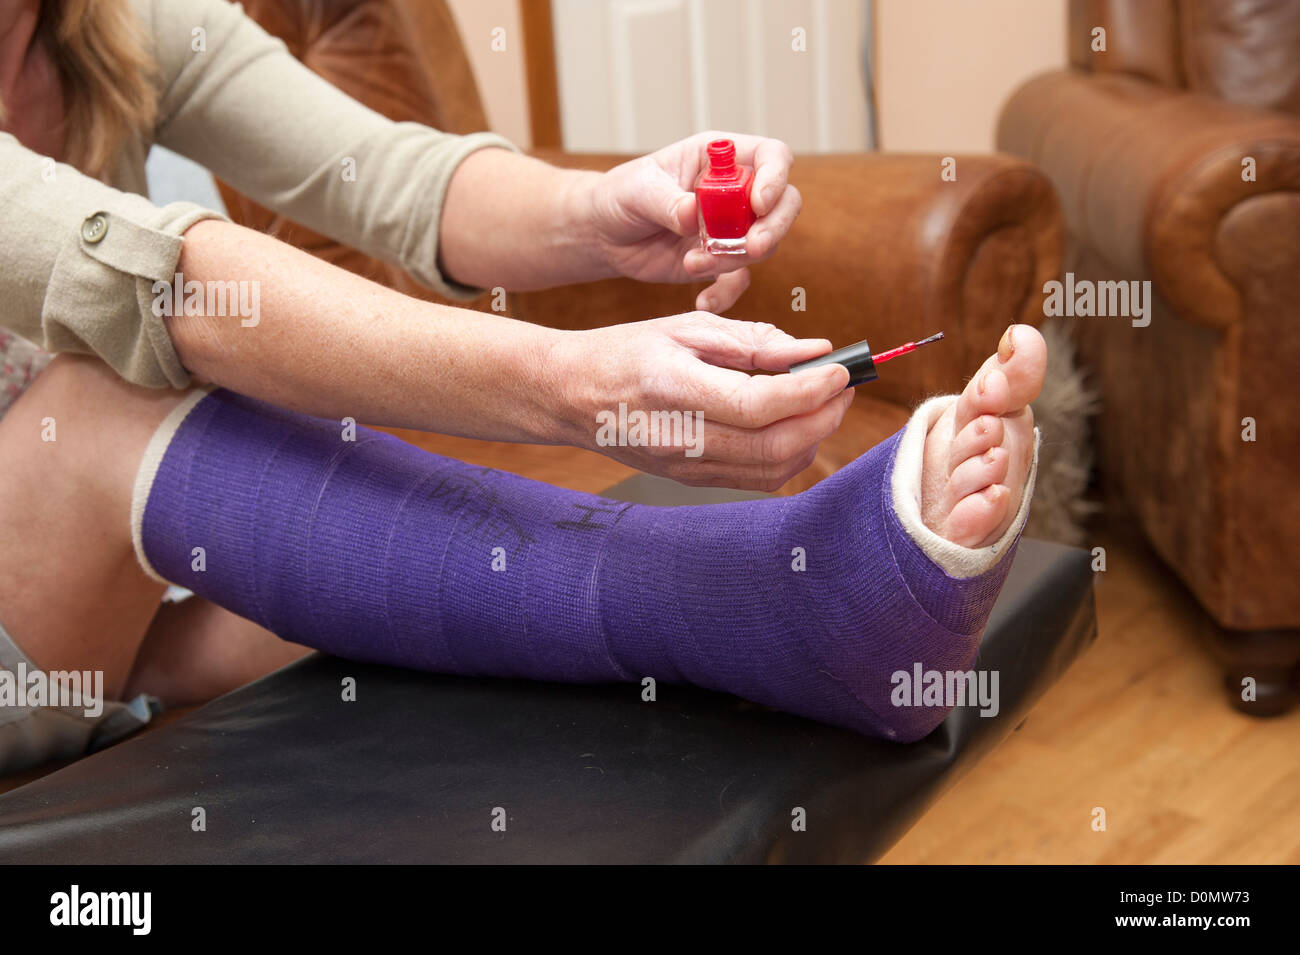

RFW025TN–In der Nähe von Broken Toe Nail mit niedlichen gemalt. Obwohl der Zehennagel ist gebrochen die Frauen wird Spaß und positiv. Zwei Füße

RFW025A6–In der Nähe von Broken Toe Nail mit niedlichen gemalt. Obwohl der Zehennagel ist gebrochen die Frauen wird Spaß und positiv. Horizontale, single